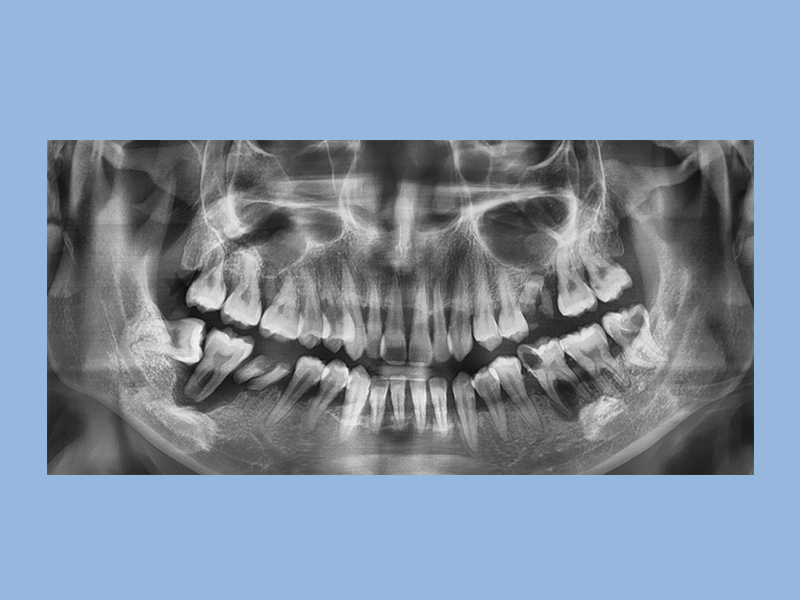

古院長不僅是每年新病例數達80位以上的 #隱適美白金精英級,更是 #中壢區 排名數一數二矯正醫師,矯正前需先給醫師評估後,再制定專屬客製的矯正計畫,搭配3D口內掃描機,影像資訊透過全球同步的數據計算,矯正者可以清楚了解牙齒每週位移的軌跡。

同時,醫師從影像中做技術評估,設計以隱適美豆豆、局部鋼絲、拉橡皮筋等工具,確實且正確的達到矯正進度。要完成整體牙齒外觀的整齊度,以及完美的咬合結果,憑藉著經驗值高的醫師專業判斷。